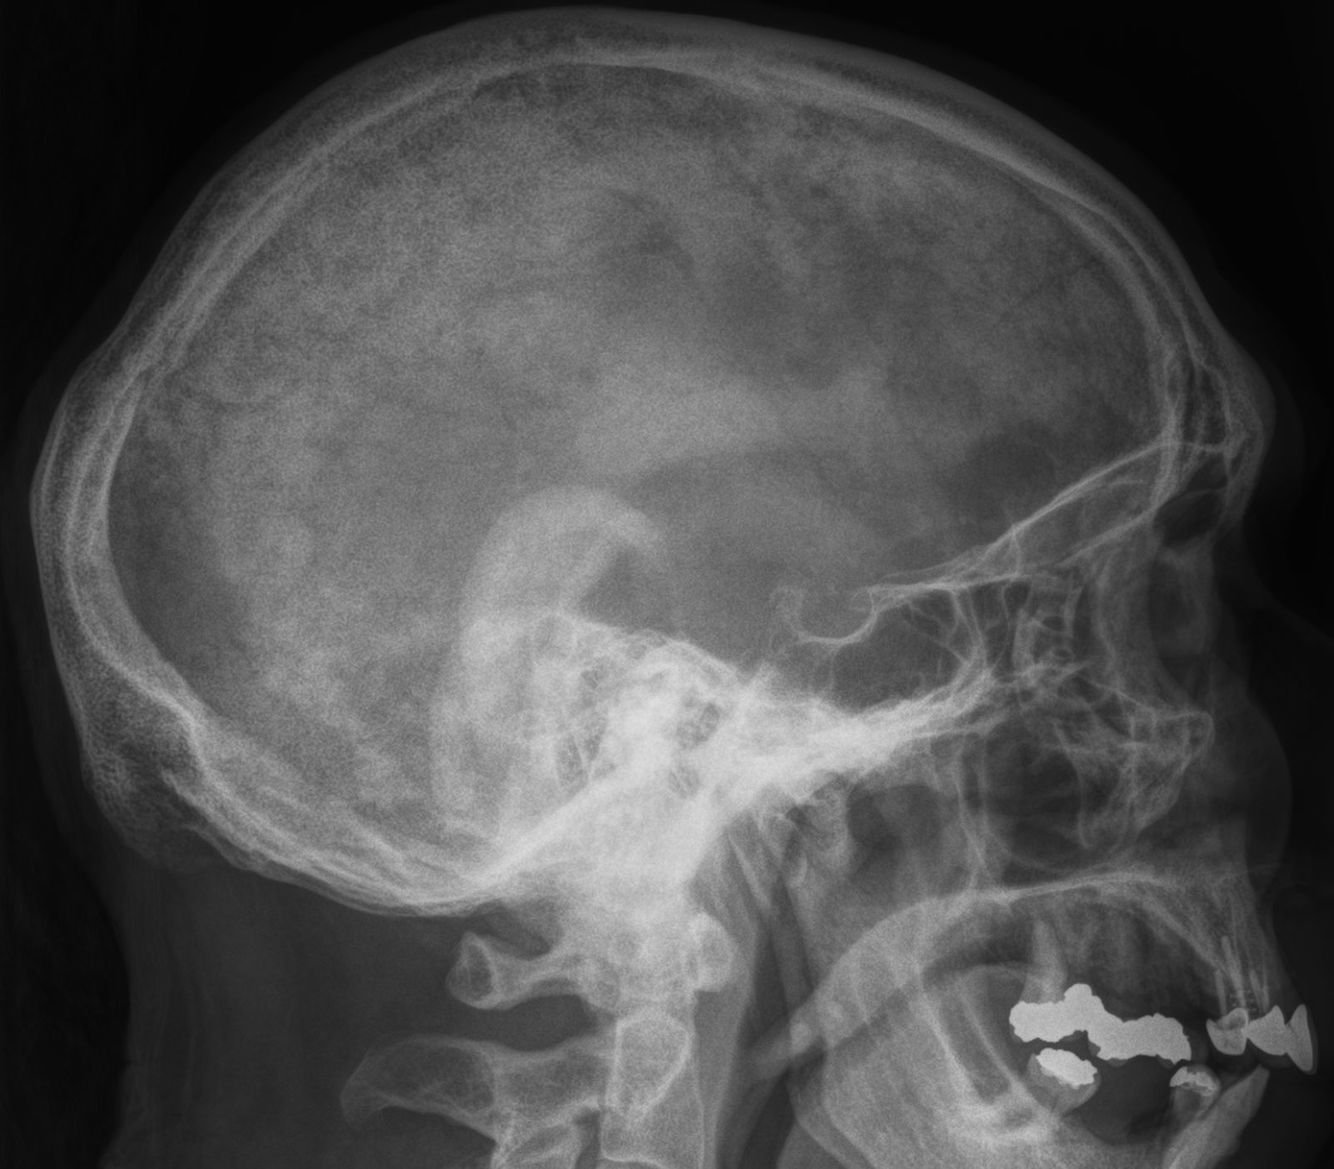

What disease does this patient have?

This is classic Pagets disease. Areas of lysis, sclerosis, and calvarial thickening.